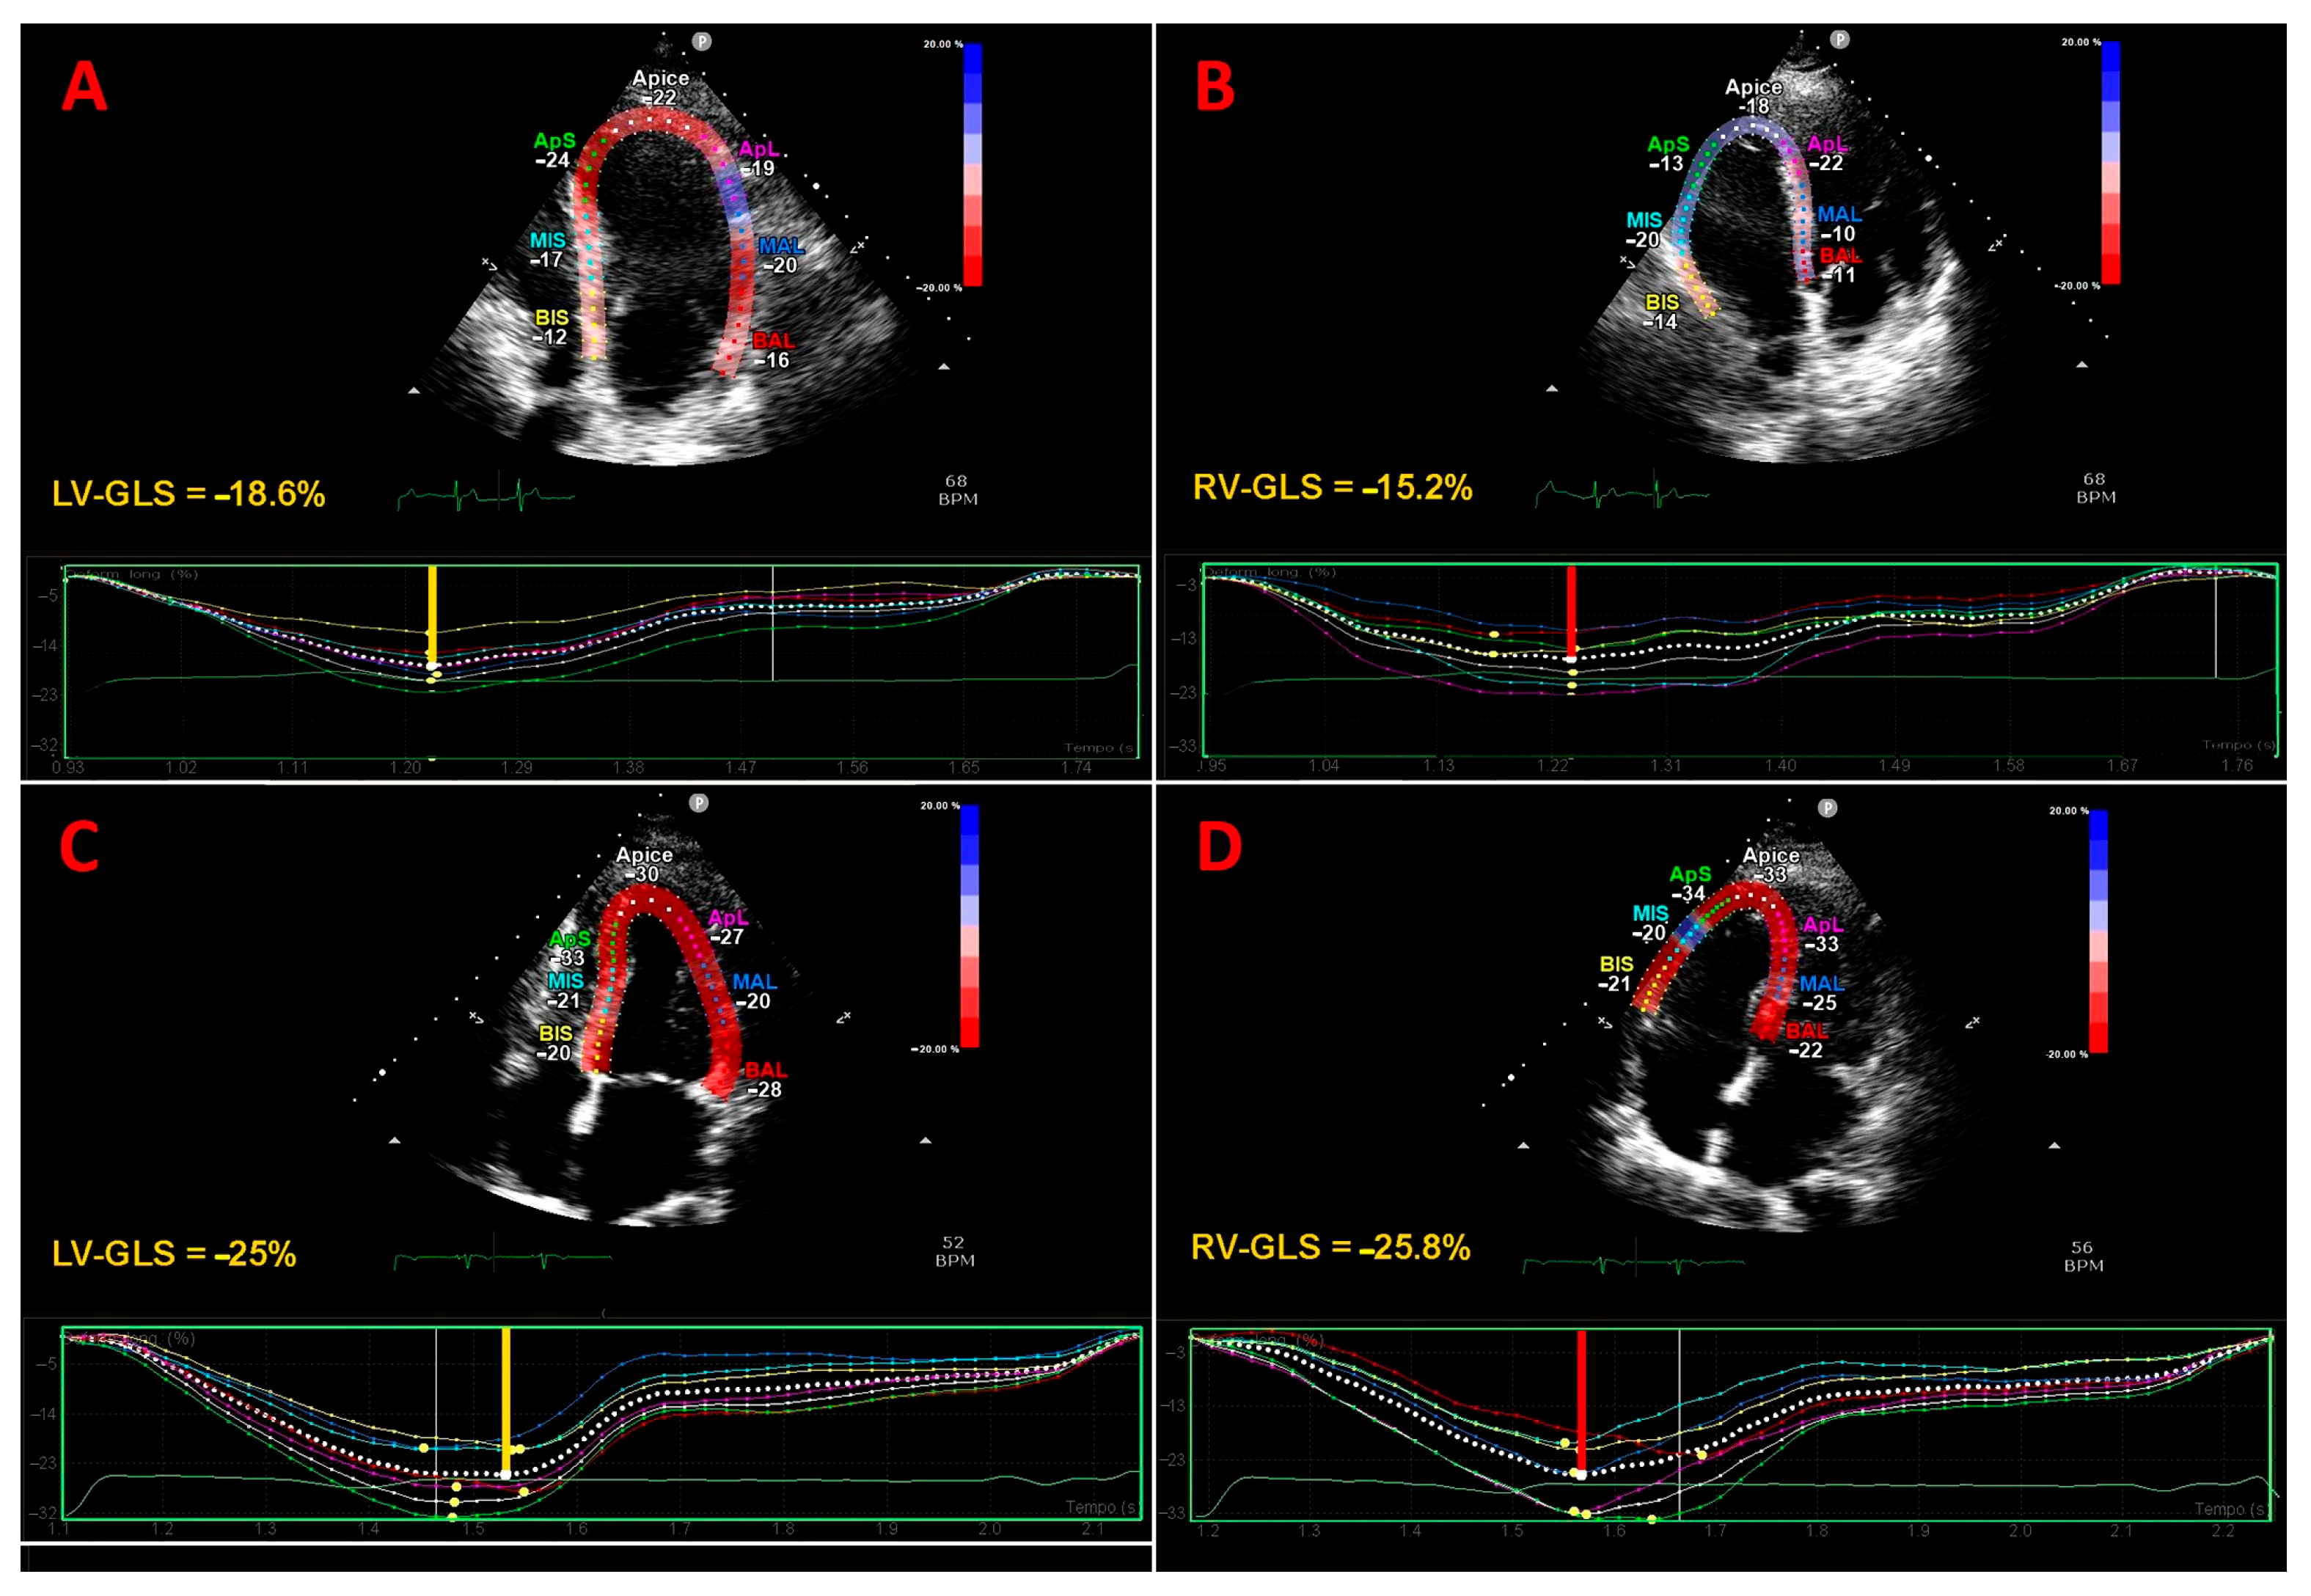

3.5. Effect of COPD on LV-GLS

3.6. Effect of COPD on RV-GLS

| LV-GLS (%) | 6 (60) | 337 vs. 172 | 17.1 (13.9−18.9) | 19.9 (17.1−22.3) | <0.05 |

| RV-GLS (%) | 5 (50) | 270 vs. 157 | 19.5 (14.6−22) | 25.4 (18.3−31) | <0.05 |